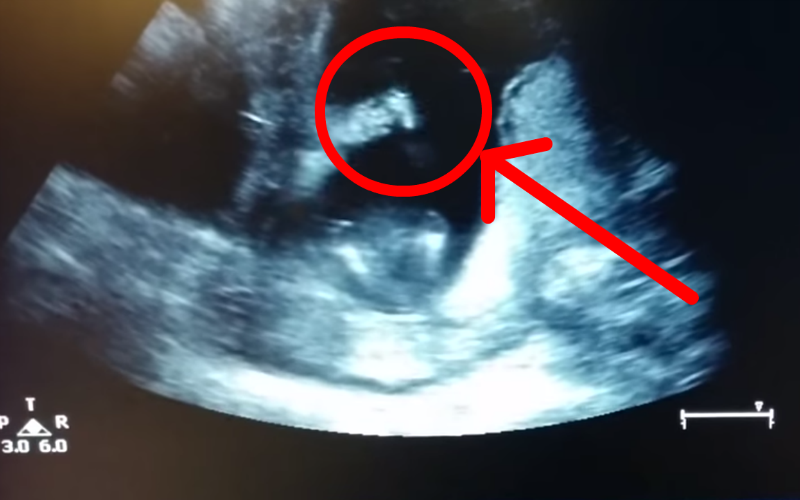

FeaturedPro-LifeVideos Did This Unborn Baby Clap Her Hands in the Womb? The Editors March 30, 2015 — 1 minute read Share this post The link has been copied! Jen Cardinal / YouTube Share this post The link has been copied!